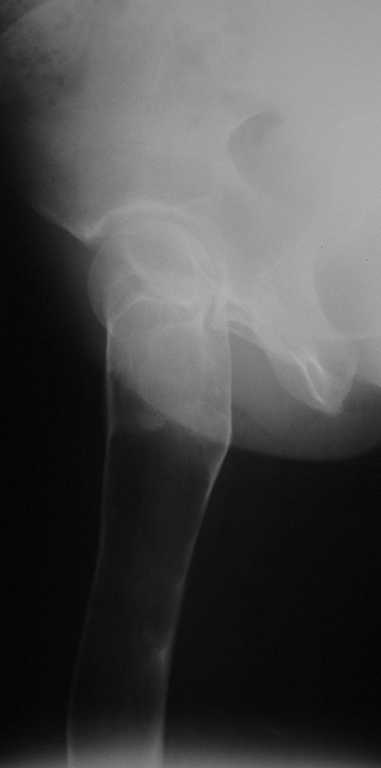

Уважаемые коллеги! В клинику поступила молодая женщина 35 лет с

жалобами на интенсивные боли в области правого бедра, носят спонтанный

характер, имеются "ночные" боли. Движения в правом тазобедренном

суставе в полном объёме, практически безболезненные. По результатам

x-ray диагностики выявлен патологический очаг, занимающий весь

проксимальный отдел и 2/3 диафиза правой бедренной кости. Другие

трубчатые кости верхних и нижних конечностей - без очагов поражения.

Имеется небольшой (1,5х2,5 см) очаг в крыле правой подвздошной кости.

По результатам трепанобиопсии проксимального отдела правой бедренной

кости - фиброзная строма и костные балки, без атипии.